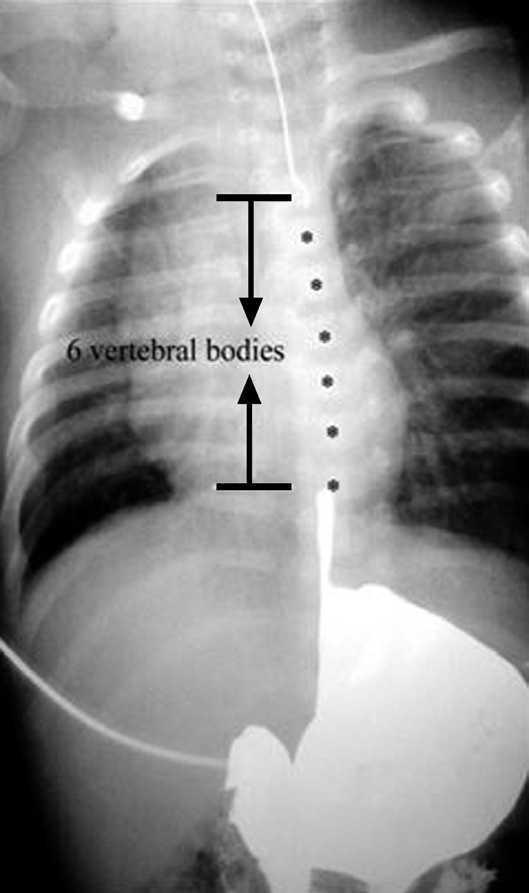

Un 5 % de las AE presentan una separación entre cabos superior a 3 cuerpos vertebrales (> 3 cm), son las formas long-gap3 (fig. 1). Suelen ser AE tipo I (atresia pura, sin fístula traqueoesofágica) y algunas tipo III (atresia con fístula traqueoesofágica distal) 3. Estos casos requieren técnicas quirúrgicas complejas, que permitan salvar la gran distancia existente entre ambos bolsones esofágicos, con suturas bajo gran tensión y riesgo de dehiscencia precoz. Precisan un cuidadoso tratamiento postoperatorio en la unidad de cuidados intensivos pediátricos (UCIP).

Figura 1. Atresia de esófago forma long-gap, distancia entre el bolsón esofágico superior y el inferior superior a 3 cuerpos vertebrales ( » unos 3 cm).